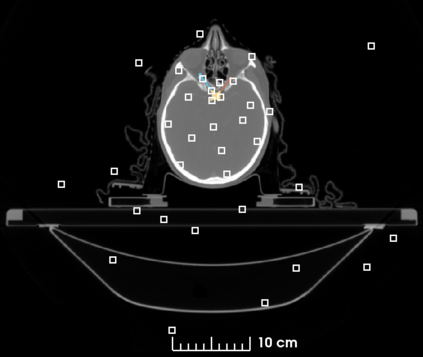

The segmentation of organs at risk (OAR) is a required precondition for the cancer treatment with image guided radiation therapy. The automation of the segmentation task is therefore of high clinical relevance. Deep Learning (DL) based medical image segmentation is currently the most successful approach, but suffers from the over-presence of the background class and the anatomically given organ size difference, which is most severe in the head and neck (HAN) area. To tackle the HAN area specific class imbalance problem we first optimize the patch-size of the currently best performing general purpose segmentation framework, the nnU-Net, based on the introduced class imbalance measurement, and second, introduce the class adaptive Dice loss to further compensate for the highly imbalanced setting. Both the patch-size and the loss function are parameters with direct influence on the class imbalance and their optimization leads to a 3\% increase of the Dice score and 22% reduction of the 95% Hausdorff distance compared to the baseline, finally reaching $0.8\pm0.15$ and $3.17\pm1.7$ mm for the segmentation of seven HAN organs using a single and simple neural network. The patch-size optimization and the class adaptive Dice loss are both simply integrable in current DL based segmentation approaches and allow to increase the performance for class imbalanced segmentation tasks.